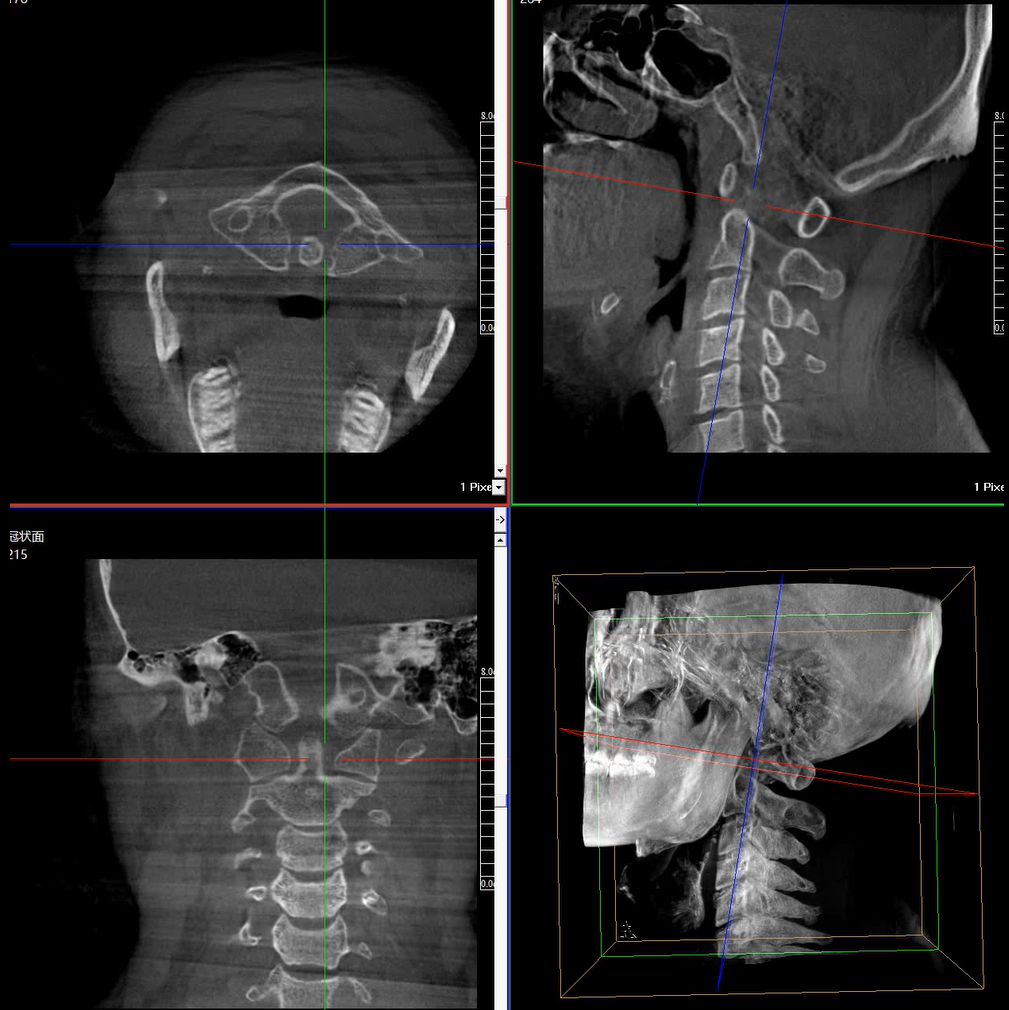

術(shù)中三維成像和橫斷面圖像提供多角度的手術(shù)診斷信息,輔助醫生進(jìn)行術(shù)中評估判斷,諸如骨折復位情況和內植入螺釘的尺寸和位置,輔助手術(shù)更好地完成。

提供更大的術(shù)中三維成像視野,采集更多圖像信息,可一次拍全全段頸椎、全段腰椎、七節胸椎、雙側骶髂關(guān)節、股骨頭及單側盆骨。